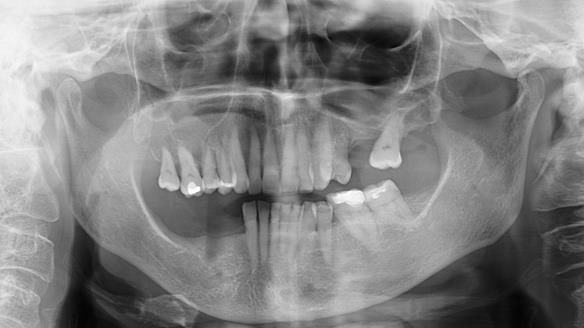

Welcome to Newsletter 61. In this edition, I walk through the process of creating and fitting a metal based lower partial denture for Joyce, a fit and healthy 76 -year-old woman.This issue shows the complete protocol workflow for achieving an exceptionally well-fitted and aesthetically good RPD.

Joyce's Case Presentation 61

Welcome to Newsletter 61. In this edition, I walk through the process of creating and fitting a metal based lower partial denture for Joyce, a fit and healthy 76 -year-old woman.

Joyce self-referred to me for specialist prosthodontics.

The missing lower right teeth to be replaced with a metal based partial denture.

Monitoring of Natural Teeth: Remaining natural teeth to be regularly monitored by General Dental Practitioner.

Soft Tissue Examination: Routine visual screening for oral cancer was conducted, and the soft tissues appeared healthy.

The detailed clinical situation and treatment process are outlined below, with clinical work provided by me and technical work by Rowan Garstang. The treatment spanned six visits for denture fitting and one review.